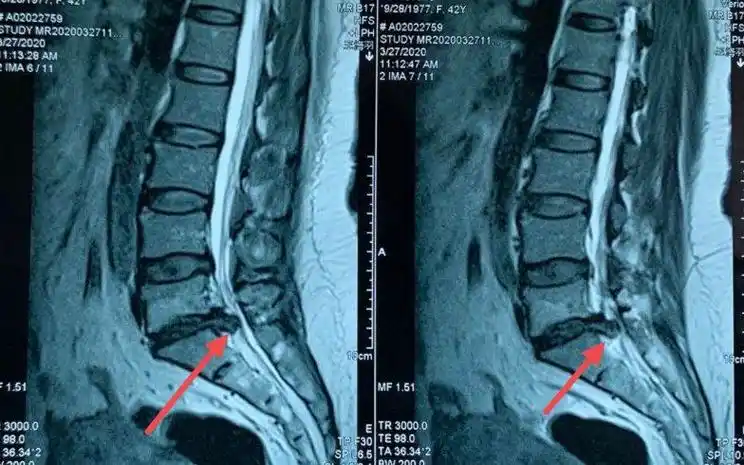

腰5/骶1椎间盘突出位置图

看下图,腰4,腰5,骶1的位置,以及红色箭头所指的腰5骶1突出的位置.